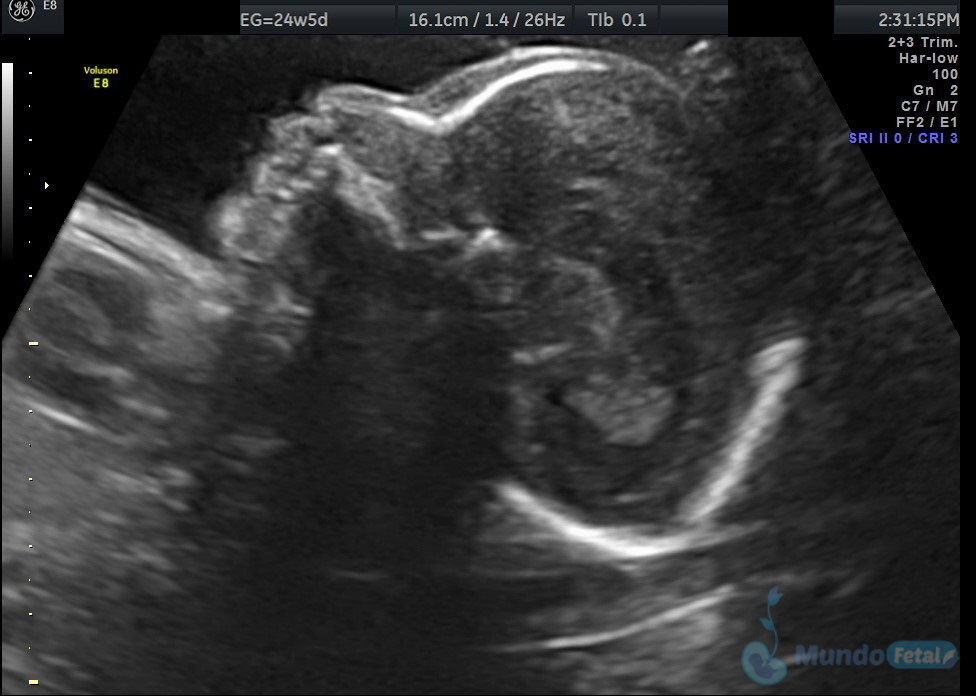

Ultrasonido 2do Trimestre 18-23 Semanas (Estructural o Anatómico)

Entre las 18 y 22 semanas, el feto ha desarrollado la mayoría de sus estructuras anatómicas, permitiéndonos valorar de manera detallada todos los órganos del bebe, descartando anomalías anatómicas fetales y datos de cromosomopatías. Prediciendo además preeclampsia (Doppler de arterias uterinas) y parto prematuro (por medio de la medición de la longitud del cérvix). En manos expertas, la detección de anomalías anatómicas supera el 80%.